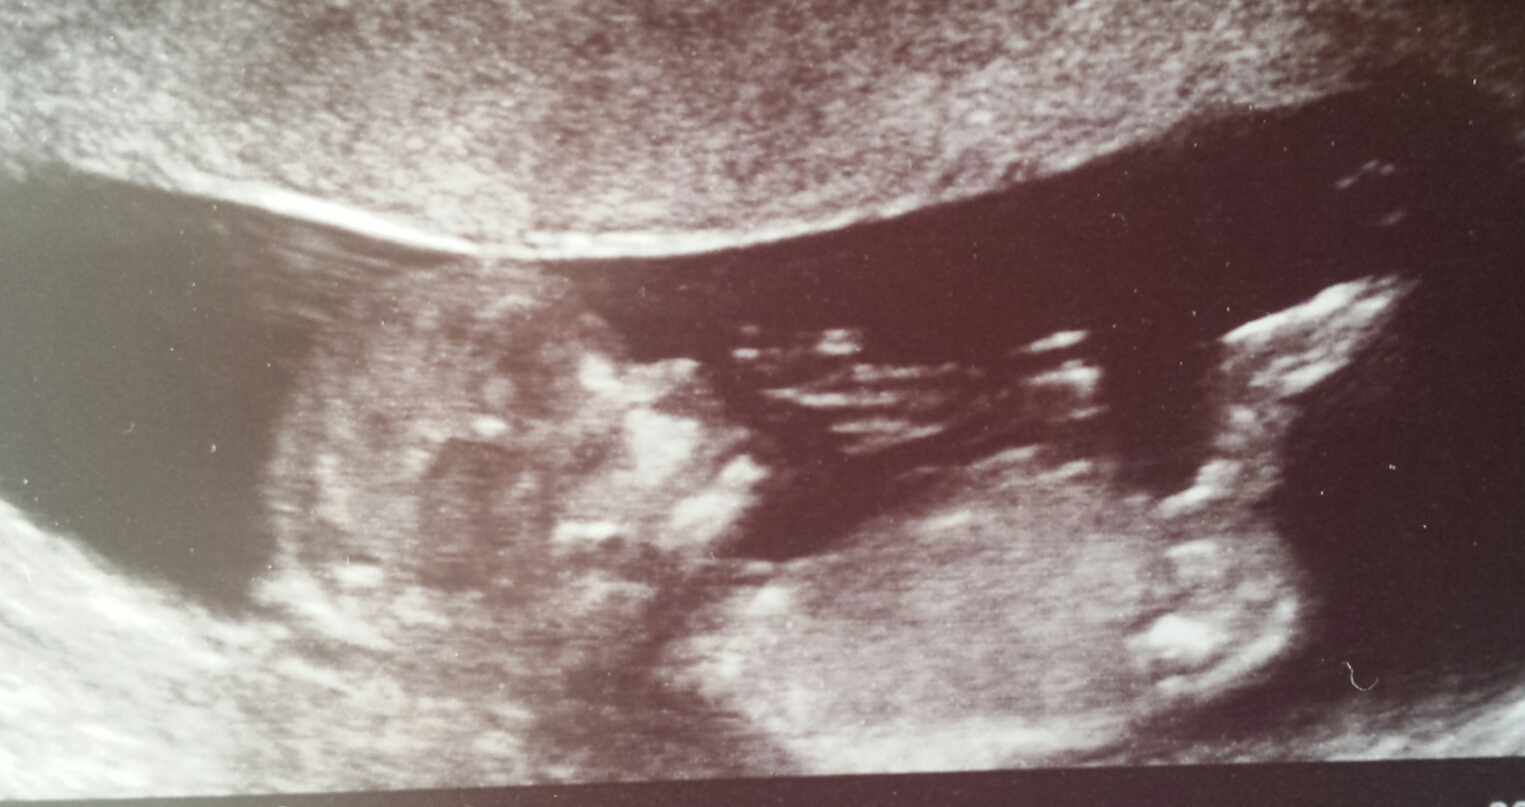

Attachment 26593

UPDATE: 16 week potty shot, said she couldn't be 100% certain but looking like a boy x

Id say boy.

Baby boy. I see no nub in the last photo.